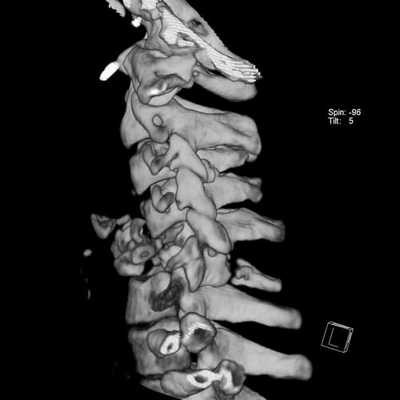

Основные отличия МРТ от КТ позвоночника кроются в принципе получения изображения. Современная компьютерная томография (или МСКТ - мультиспиральная компьютерная томография) основана на способности по-разному, в зависимости от плотности тканей, поглощать рентгеновское излучение. Особенности мультиспиральной компьютерной томографии позвоночника заключаются в том, что в ходе процедуры собираются множественные непрерывно перекрывающиеся срезы. Это дает возможность производить компьютерную обработку данных с последующим созданием объемных, так называемых 3D изображений и реконструкций. Полученные на МСКТ позвоночника снимки врачи могут рассматривать на экране с любой стороны как в режиме индивидуального просмотра, так и в режиме анимации, когда объект вращается вокруг своих осей. Используя специальные функции разворота и обрезки, можно выделить интересующую область и визуализировать ее с любой стороны. Это дает возможность медикам видеть скрытые структурные повреждения.

МРТ позвоночника дает возможность хорошо визуализировать спинной мозг, мягкие ткани, грыжу межпозвоночного диска. В случаях, когда неврологам, травматологам и хирургам необходимо получить трёхмерную реконструкцию и исследовать кости позвоночника в разных плоскостях или диагностировать обызвествление межпозвоночного диска, применяется КТ позвоночника.